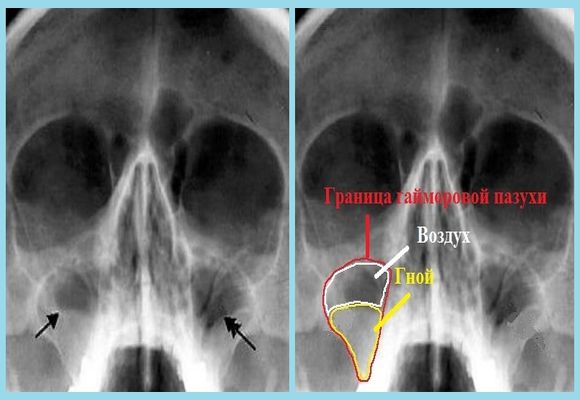

Подобное нарушение можно визуально определить на обычном рентгеновском снимке, где в области нахождения жидкой субстанции наблюдается темное пятно. Провести имитацию рентгенологического исследования можно и в домашних условиях, воспользовавшись электрическим фонариком и погасив свет. Для этого потребуется вставить фонарик в рот, включить его и рассмотреть область носа. Если у вас гайморит, то верхняя часть будет затемнена.

- Рентген. Признаки гайморита на рентгеновском снимке включают затемнения в области воспаления и заполненные гнойной слизью носовые пазухи.

Выраженное отечение слизистых оболочек носа и накопившиеся в них гнойные массы на рентген-снимке будут видны как затемненная область. Характерным признаком гайморита будет также то, что на снимке гнойные образования будут отображены в нижнем отделе пазух носа.